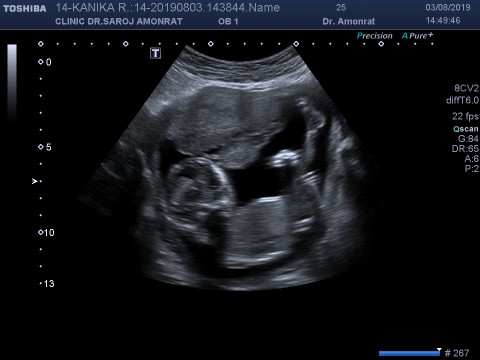

14 วีคค่ะ

14w3dคะ